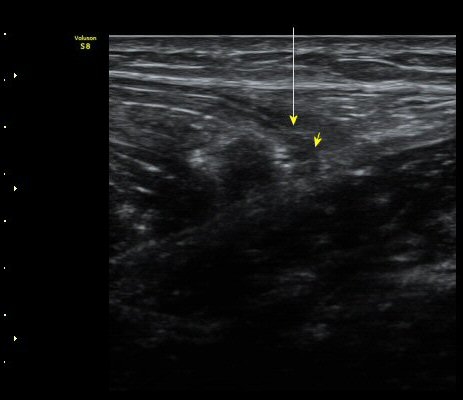

¼ö»ó ÈÄ 2ÁÖ Â°

³»Ãø ºñ·Ï±Ù Á¾´Ü¸é°Ë»ç¿Í Ⱦ´Ü¸é°Ë»ç¿¡¼­ ºñº¹±Ù°ú °¡Àڹ̱ٻçÀÌ¿¡ Ç÷¾×ÀÌ °í¿© ÀÖÀ½

(±×¸² 5, 6, 7).